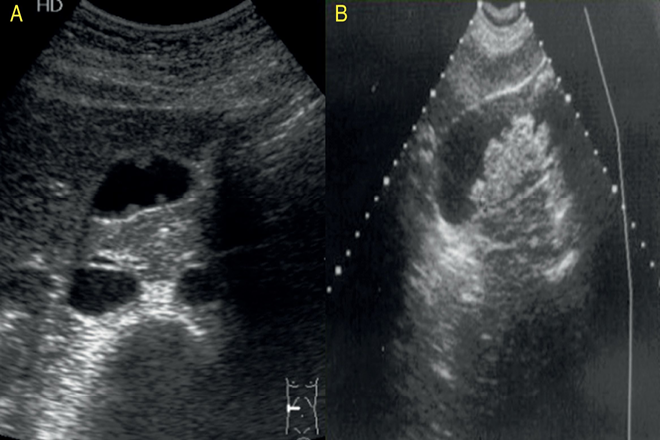

La vesícula biliar es una pequeña bolsa de 7 a 10 cm de longitud y de 3 a 5 cm de ancho, con capacidad de 30 a 50 ml, tiene la forma de pera y se encuentra adherido por el peritoneo al parénquima hepático, esta se divide en 4 porciones anatómica que son: el fondo, cuerpo, infundíbulo y cuello.

El colédoco tiene una longitud aproximadamente de 8 a 11.5cm y un diámetro de 6 a 10 mm. La porción superior está situada en el borde libre del ligamento  hepatoduodenal, a la derecha de la arteria hepática propia y por delante de la vena porta. El tercio medio del colédoco forma una curva a la derecha por detrás de la primera porción del duodeno, donde se separa  de la vena porta y de las arterias hepáticas. El tercio inferior se curva mas a la derecha por detrás de la cabeza del páncreas, en el que forman  un surco, y desemboca en el duodeno a través del ámpula de váter, donde a menudo se le une al conducto pancreático.

El colédoco distal es difícil de visualizar debido a el gas abundante del duodeno y la flexura hepática.

Se utiliza una proyección oblicua subcostal con el borde izquierdo del transductor mas cefálico que el borde derecho, la cara del transductor se dirige hacia el hombro derecho. Interrumpiendo la respiración profunda, un barrido del transductor dirigido desde el hombro hasta la región umbilical mostrara la vena hepática media y después el eje longitudinal de los conductos hepáticos derecho e izquierdo, seguido del colédoco en sección transversal. Rotando el transductor a 90º  respecto a este plano, una segunda interrupción de la inspiración permitirá ver el eje longitudinal del colédoco y el hepático común en el hilio hepático.